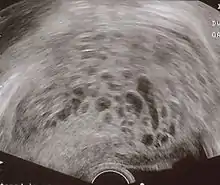

Диагноз пузырного заноса устанавливается при ультразвуковом исследовании. Вместо нормальной структуры плодного яйца обнаруживается пестрая картина, получившая название «снежной бури». В яичниках определяются лютеиновые кисты. При исследовании гормонов отмечается высокий уровень хорионического гонадотропина (ХГЧ), иногда многократно превышающий уровень при нормальной беременности.